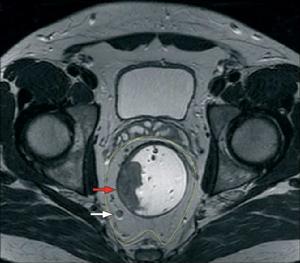

①水平位斷層解剖顯示直腸及其系膜被直腸固有筋膜所包裹,此筋膜後側與骶前筋膜相貼,外側與髂內血管和盆腔神經叢毗鄰,前側與Denonivillers筋膜相貼;屍體MRI顯示,直腸固有筋膜呈低信號、細線狀包繞直腸系膜;活體MRI顯示與屍體MRI顯示一致。

③冠狀位斷層解剖顯示,直腸固有筋膜沿直腸系膜外側下行,與肛提肌表面的壁層筋膜構成一“V”字形直腸外間隙;屍體MRI顯示,直腸固有筋膜呈縱行、低信號結構,直腸系膜呈高信號;活體MRI顯示與屍體MRI顯示基本一致。

①術前MRI發現,直腸固有筋膜呈低信號、線狀圍繞在直腸系膜周圍,與癌腫邊緣的關係清晰可見。